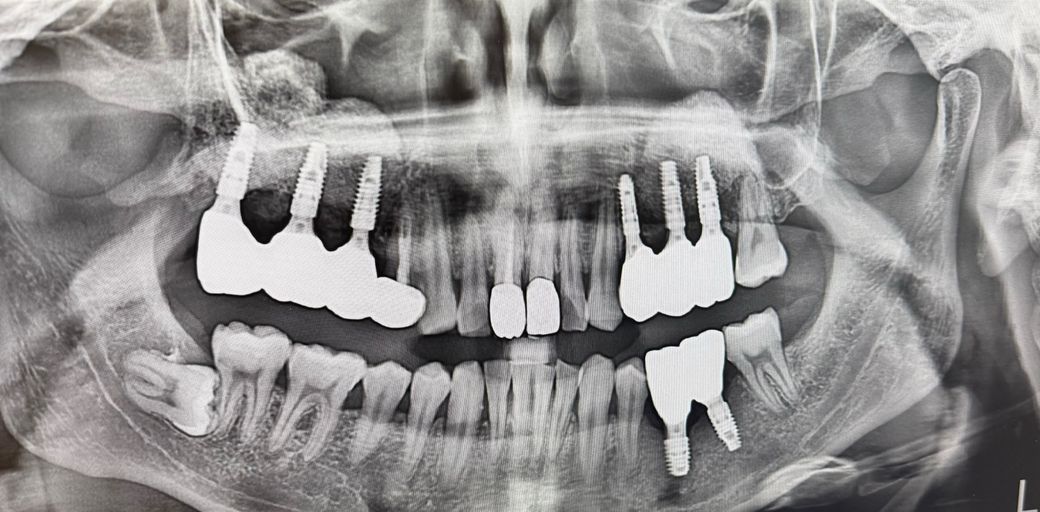

상악동거상술 하고 6개월 대기 후 보철물까지 식립하고 6개월 가량 지난 사람입니다.

12/24일에 파노라마 찍은것과 보철물 식립전의 잇몸사진도 첨부하겠습니다

• 3번 째 사진

엑스레이상으로 크게 문제가 있는 염증상태는 아닙니다 그냥 보철물 종류(pfm)에 따라 안쪽 메탈 부위가 비쳐보이는 것이거나 어버트먼트 부위가 보이는 겁니다